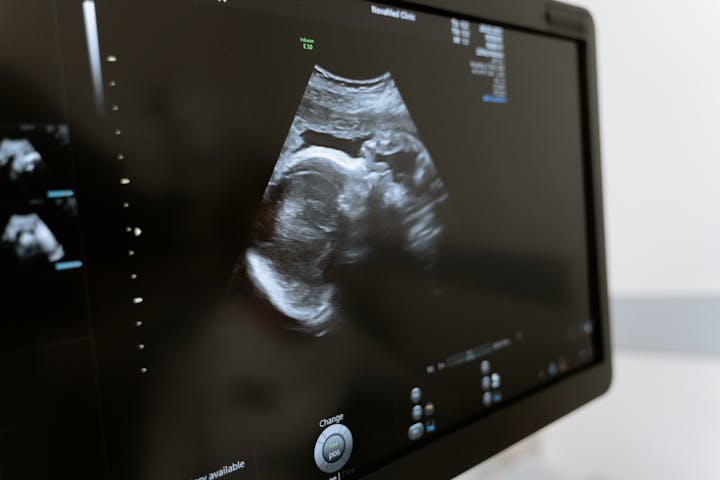

1. USG (Ultrasonografi)

USG adalah metode yang paling umum digunakan untuk menentukan jenis kelamin bayi. Akurasinya mencapai 95-99 persen jika dilakukan oleh ahli berpengalaman pada usia kehamilan yang tepat. USG untuk mengetahui jenis kelamin janin bisa dilakukan pada usia kehamilan 18-22 minggu.